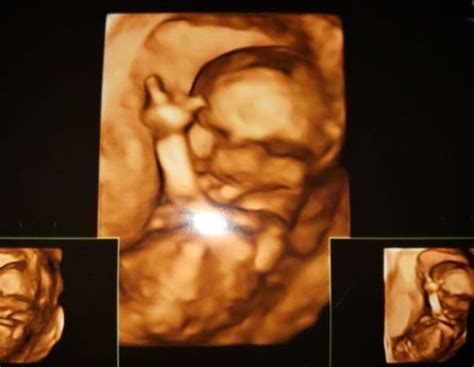

4D ultrazvuk je technológia, ktorá zobrazuje bábätko v trojrozmernom obraze v reálnom čase. Zatiaľ čo 3D predstavuje trojrozmernosť obrazu, štvrtá dimenzia (4D) pridáva čas, čo umožňuje sledovať aktuálne pohyby dieťaťa a jeho mimiku. Na rozdiel od klasického 2D ultrazvuku, 4D ultrazvuk poskytuje omnoho plastickejší a detailnejší pohľad.

Zatiaľ čo 3D ultrazvuk poskytuje trojrozmerný, ale statický obraz bábätka (najčastejšie jeho tváričku), 4D ultrazvuk pridáva rozmer pohybu v reálnom čase. Vďaka 4D ultrazvuku môžete sledovať, ako sa bábätko práve hýbe, mračí, usmieva alebo hýbe ručičkami. Výsledkom je nielen fotografia, ale aj video záznam.

Pri 3D ultrazvuku je pre pekné fotografie dôležité, aby sa bábätko pozeralo smerom k sonde a nemalo pred sebou ruky či nohy. Ideálny čas na 3D ultrazvuk je po 16. týždni, kedy je možné vizualizovať väčšiu časť plodu naraz. Po 24. týždni už vieme vizualizovať tvár, ktorá má dostatok podkožného tuku a podobá sa na budúceho novorodenca.